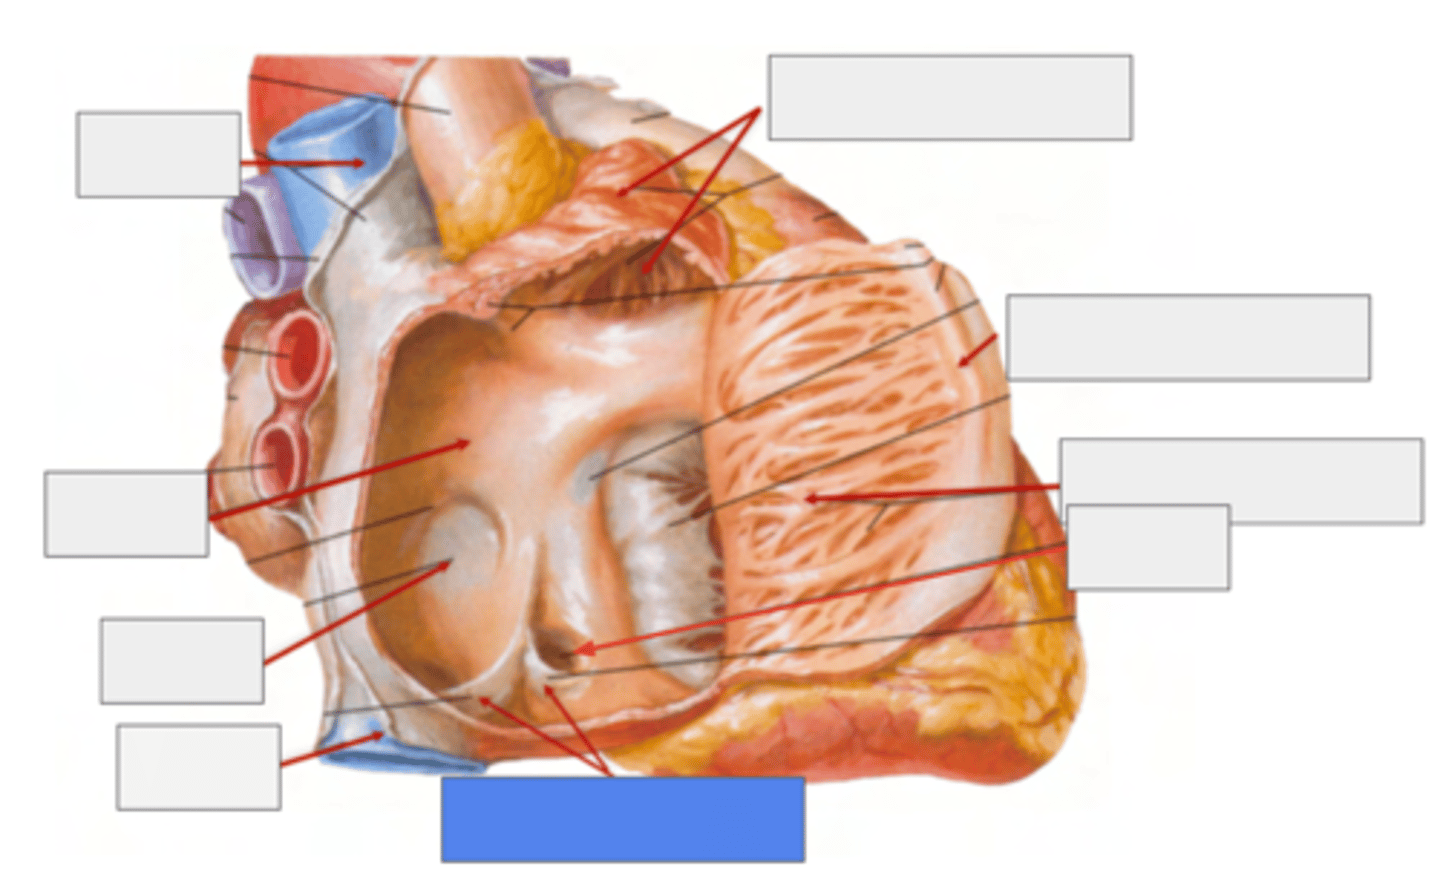

What is pointing the blue square?

valves of inferior vena cava and coronary sinus